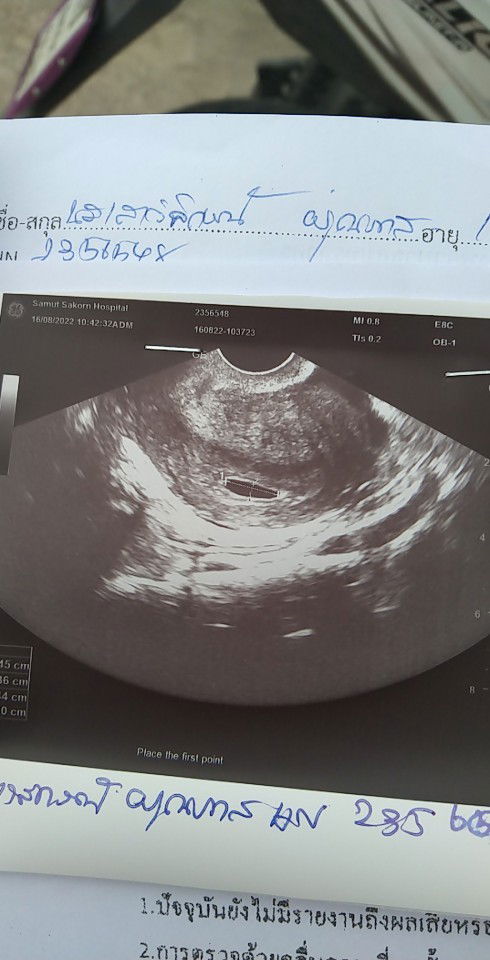

มาท้อง2 รู้ว่าท้องได้ประมาน1เดือนกว่าๆ อัลตราซาวด์ คุณหมอบอก อายุครรภ์ประมาน40วัน อัลตราซาวด์ใช่เครื่องสอดอวัยวะเพศค่ะ อยากทราบว่า ที่กลมๆๆนี่ คือถุงน้ำคล่ำใช่ไหมค่ะ เเละปกติดีไหมค่ะ ถามพยาบาล พยาบาลไม่ให้คำตอบค่ะ เขาบอกว่ายุ่งอยู่ ขอรบกวนถามหน่อยนะคะ ขอบคุณค่ะ🙏🥰